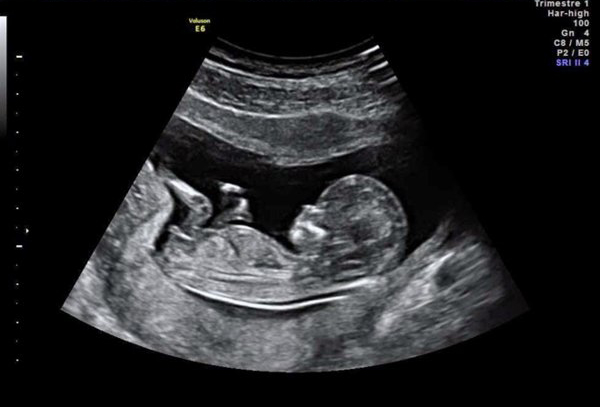

Cách tính ngày dự sinh chính xác bằng siêu âm

Siêu âm thai kỳ là cách tính ngày dự sinh chính xác nhất mà mẹ bầu nào cũng cần lưu ý. Theo các chuyên gia, mẹ bầu có thể tính ngày dự sinh chuẩn kể từ khi siêu âm ở tuần thứ 12 của thai kỳ.

Dựa vào việc kiểm tra sức khỏe, các thông số biểu hiện sự phát triển của thai nhi mà bác sĩ có thể tính được tuổi thai và từ đó sẽ dễ dàng tính được ngày dự sinh dựa vào sự phát triển của thai nhi trong 40 tuần. Do đó, mẹ bầu cần đi siêu âm đúng các mốc để nắm được các thông tin về tình hình phát triển của em bé.

Với cách tính ngày dự sinh này, chị em sẽ không cần phải nhớ chu kỳ kinh cuối bởi máy siêu âm có thể tìm thấy bào thai trong tử cung khi thai nhi còn rất nhỏ. Cụ thể:

- Sau khoảng 6 tuần, máy siêu âm có thể tìm thấy tim thai và có thể đo được chiều dài đầu mông để xác định tuổi thai.

- Tuần 24 - 30, bác sĩ có thể đo được đường kính lưỡng đỉnh để xác định ngày dự sinh chuẩn nhất. Và từ tuần thứ 30, các thông số này sẽ không còn chính xác nữa.